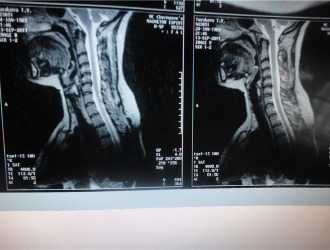

- МРТ позвоночника. Применяется для детальной оценки состояния мягкотканных структур. Выявляет стеноз или окклюзию субарахноидального пространства, утолщение связок, сдавление участков спинного мозга, зоны отека, демиелинизации, контузии или миеломаляции нервных тканей.